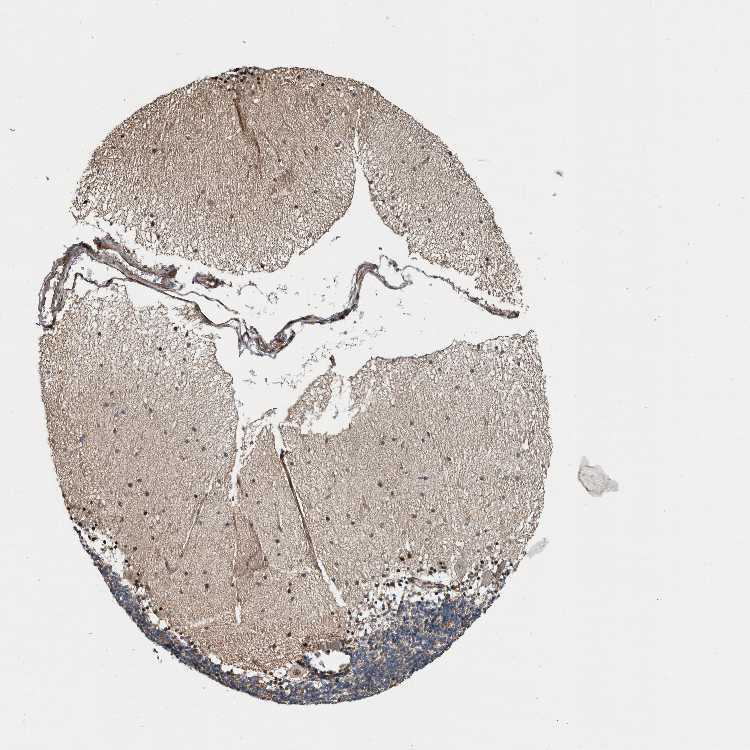

CEREBELLUM - Antibody stainingi

Antibody staining in the annotated cell types in the current human tissue is reported as not detected, low, medium, or high, based on conventional immunohistochemistry profiling in selected tissues. This score is based on the combination of the staining intensity and fraction of stained cells.

Each image is clickable and will lead to virtual microscopy that enables deeper exploration of all samples and also displays staining intensity scores, fraction scores and subcellular localization as well as patient and tissue information for each sample.

Antibody HPA023911Antibody HPA023950Antibody HPA024815

Purkinje cells HighLowMedium

Cells in granular layer MediumHighNot detected

Cells in molecular layer HighHighNot detected